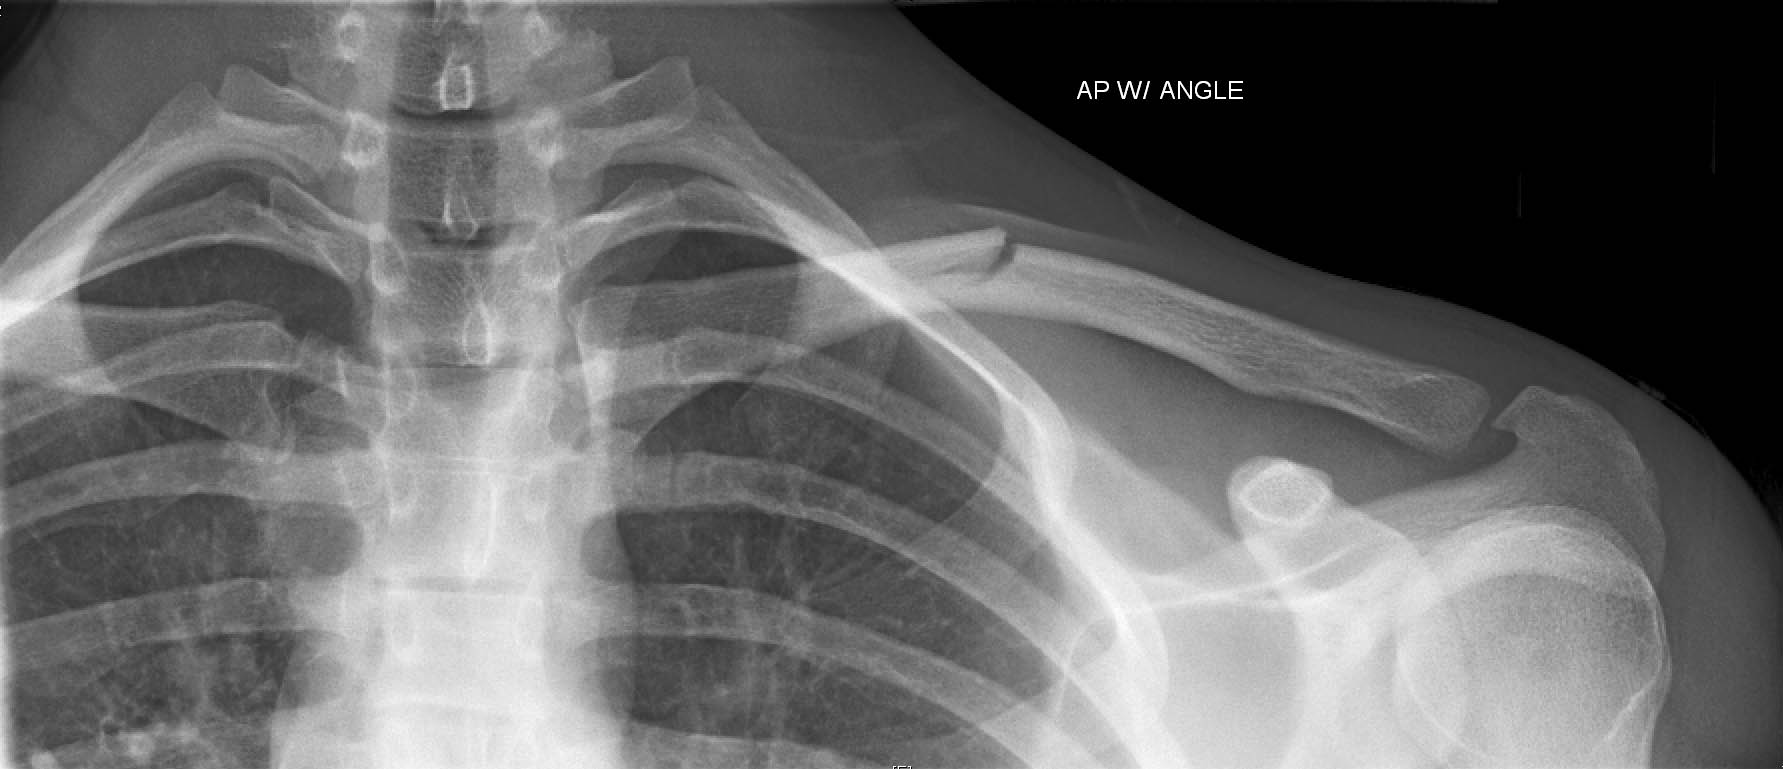

以身体部位从上到下来分别来看。先来看看肩部,如果肩部受伤大家记得骨折最容易发生的部位是哪吗?对,就是锁骨骨折,锁骨骨折时,有什么表现呢?病人的头向患侧偏斜、出现异常活动、患侧肩部下垂。

而肩部受伤引起的脱位,那就是肩关节脱位。有什么表现呢?当发生肩关节脱位时,病人出现方肩畸形、关节盂空虚,以及弹性固定导致的搭肩试验阳性。